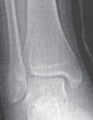

19. Many Salter type II fractures can be successfully stabilized with two 0.062-inch smooth Kirschner wires.

1. The wires are placed from distal to proximal, from the anteromedial malleolus and from the anterolateral corner of the tibial epiphysis (

TECH FIG 2

).

A B C DTECH FIG 2•

Treatment of Salter-Harris type II supination–external rotation (SER) type of fracture with interposed periosteum.

A,B.

Radiographs demonstrate a Salter-Harris type II SER type of fracture gapped anteriorly.

C.

Periosteum (shown in red) is often interposed anteriorly in SER-type Salter-Harris II fractures, which prevents closed reduction.

D.

This periosteum must be carefully extracted from the physeal fracture to obtain anatomic reduction and decrease the chance of premature physeal closure.

(continued)

TECHNIQUES E F G HTECH FIG 2•

(continued)_E,F. Open reduction was obtained after failed closed reduction due to interposed periosteum in the physeal fracture. Then the fracture was stabilized with two crossed Kirschner wires placed percutaneously. G,H. At 1 year postoperatively the distal tibial physis appears open. The _red arrows

mark the Harris growth line, which is parallel with the physis, demonstrating symmetric growth after injury. This further supports that the tibial physis is open.